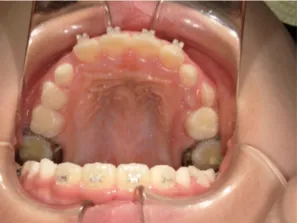

治療前①小1(7y2m):初診

*上顎前歯後方傾斜、上下唇の突出、口唇閉鎖不全傾向、コンケーブなし

| カウンセリング・診断結果 | 骨格的に下顎前方位で下顎骨も大きいタイプで、上の前歯が後ろに傾斜している受け口です。 顔立ちは上下唇が突出していて口唇閉鎖不全傾向がありますが、コンケーブにはなっていません(写真①)。 機能的に低位舌があり、今後受け口を助長する可能性があります。 受け口は、上顎骨の骨格的な前方向の成長を阻害し下顎が前へ強く成長していくため、骨格的な受け口が悪化し永久歯の咬合治療が難しくなり、症例によっては外科的な治療が必要になることがあるため早期に改善し骨格的な悪化を予防する説明をしました。 |